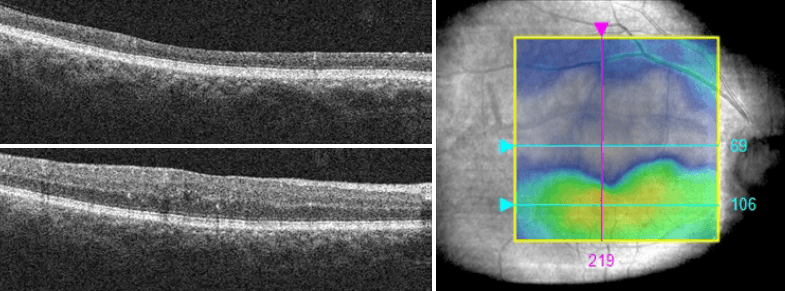

Management and Treatment of Mild and Moderate Non Proliferative Diabetic Retinopathy with Diabetic Macular Edema

Though mild and moderate NPDR may pose minimal risk to vision, DME is the most common cause of vision loss in diabetic patients. DME can occur at any stage of diabetic retinopathy. Patients with nonfoveal DME but not CSME should be counseled on the potential for vision loss and monitored every 1-4 months. Fundus photography and OCT imaging aids in the detection and management of DME. The ZEISS CIRRUS OCT overlays ETDRS sectors on the retinal thickness map to help determine the risk that DME poses on vision. DME patients with vitreomacular traction or an epiretinal membrane may be at higher risk for DME progression. Patient’s with CSME should be referred to an ophthalmologist experienced in the treatment of diabetic retinal disease.

https://covalentcareers3.s3.amazonaws.com/media/original_images/9.png

Figure 8: Sequential CIRRUS OCT imaging and Macular Change Analysis documents a resolution of diabetic macular edema.